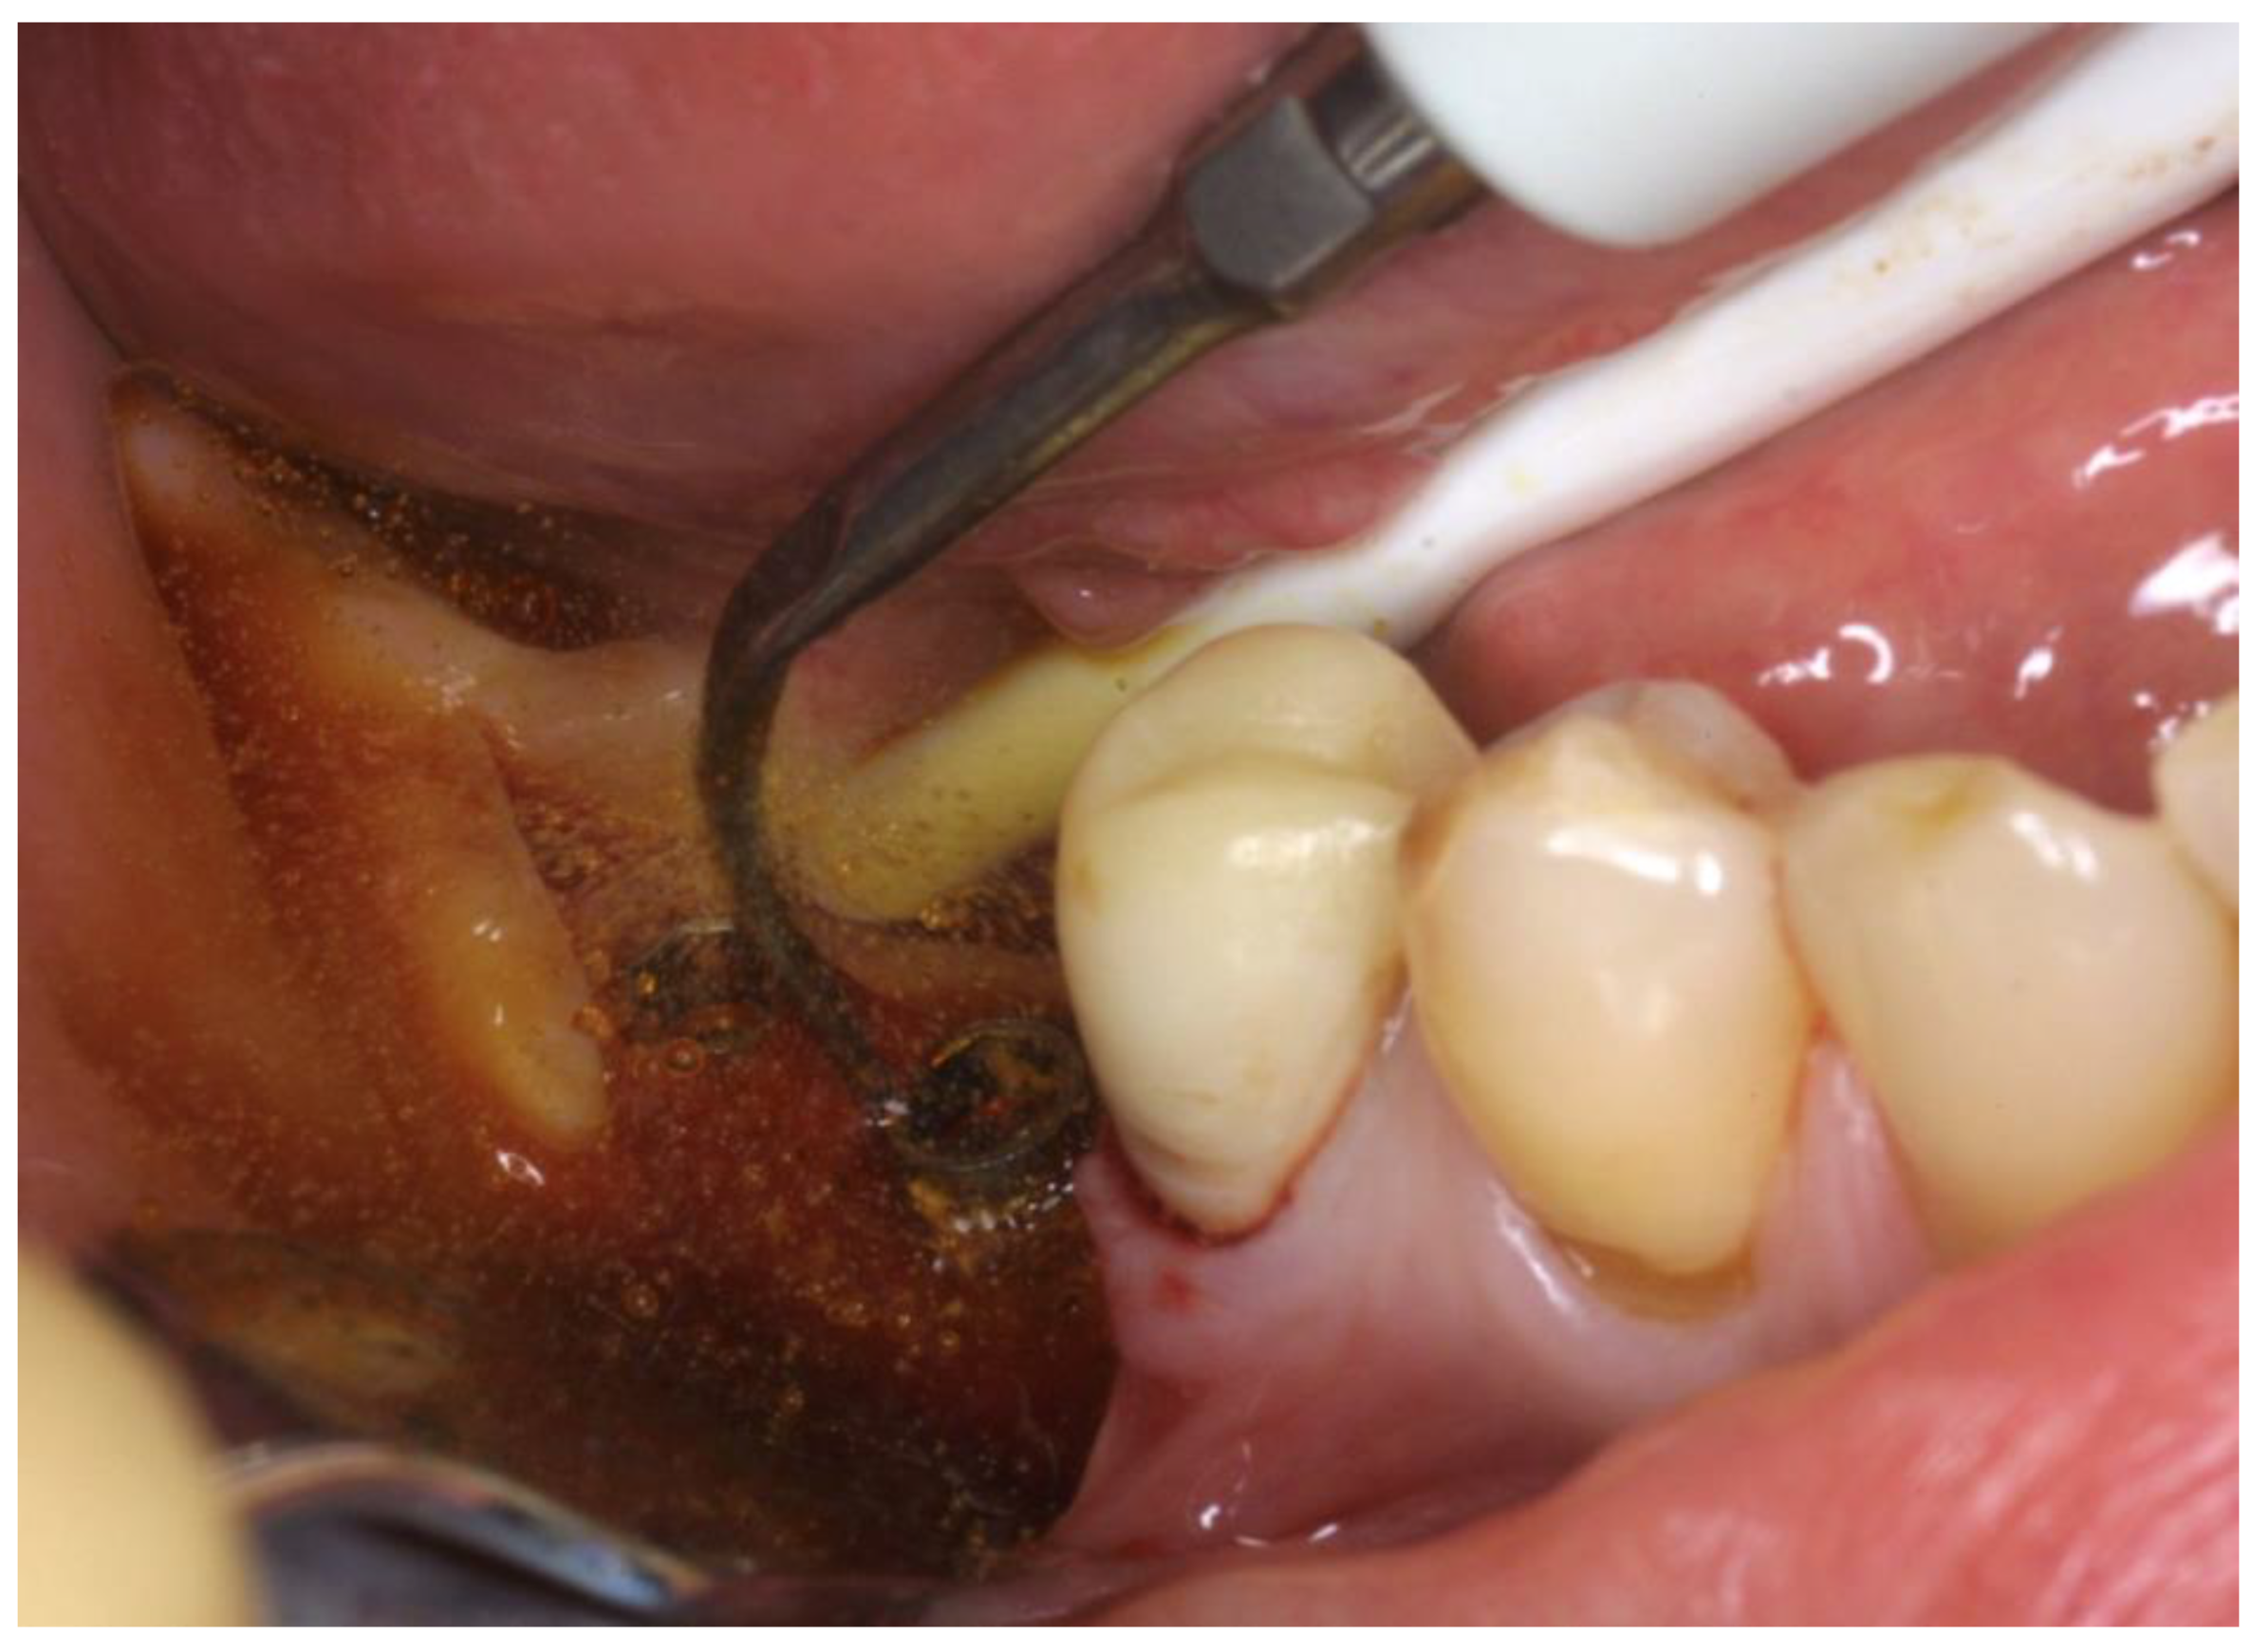

The OHLLT + Erbium:Yag surgical procedure consists of: local anesthesia; intrasulcular incision for a full thickness periodontal flap; Er:YAG laser (Pluser, Doctor Smile, Vicenza, Italy) first applied in order to remove granulation tissue (power: 1.8 W, frequency: 35 Hz, energy: 50 mJ, water: 20%, air: 60%); ultrasonic instrumentation for supra- and subgingival scaling combined with water–Betadine irrigation (5:1 ratio); air flow device with sodium bicarbonate powder (highly abrasive powder); subsequently, the OHLLT protocol was performed (Wiser diode laser, Sioxyl Solution, Doctor Smile, Vicenza, Italy): irrigation of peri-implant pockets with Sioxyl Solution; aspiration of Sioxyl Solution emerging from the gingival sulcus and leaving the remaining solution inside the pocket for 2 min; introduction of the HF Diode Laser Fiber 400 microns within the pocket and reaching the bottom, radiation of subgingival tissues with a back and forth movement using the dedicated program, 60 s per side (2.5 W peak power, high frequency, 10 KHz, power average 0.5 W, fluency 25,000 J/cm2, 416.66 J/cm2 per second). After the decontamination with OHLLT, the Er:YAG laser (Pluser, Doctor Smile) was used to treat implant surfaces (power: 0.8 W, frequency: 10 Hz, energy: 80 mJ, water: 60%, air: 60%) and then to create mechanical biostimulating effects on bone tissues (Figure 5) (power: 3.2–3.8–4.4 W, frequency: 20 Hz, energy: 160–190–220 mJ, depending on bone density, from lower to higher, water: 70%, air: 80%). Finally, a graft mix consisting of Bio-Oss granules, autologous bone chips, platelet-rich fibrin (PRF) and collagen membranes (45% Bio-Oss, 45% PRF, 10% autologous bone chips) was applied, finalizing with flap repositioning and suturing.

Figure 5. Er:Yag (Pluser, Doctor Smile) in action on bone surfaces (power: 3.2–3.8–4.4 W, frequency: 20 Hz, energy: 160–190–220 mJ, depending on bone density, from lower to higher, water: 70%, air: 80%).